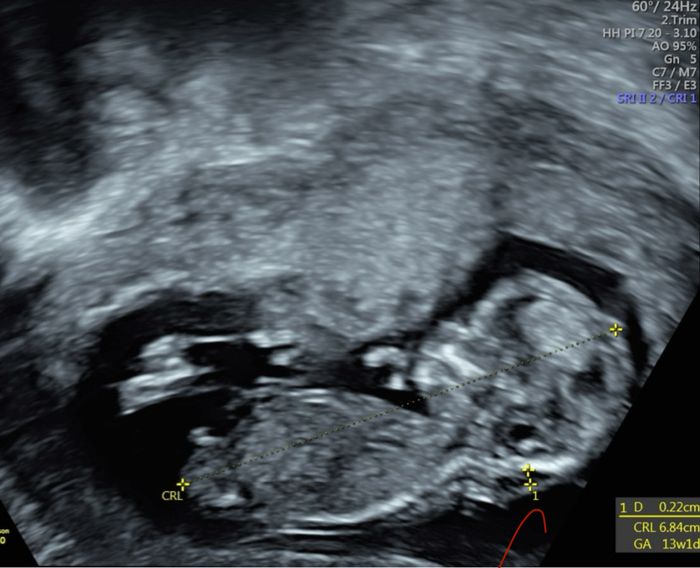

Ciao ragazze, lunedì scorso ho fatto eco genetica a 11+5 ma bebè misurava 12 settimane, ho fatto dna fetale che dovrebbe arrivare questa settimana, ma nel frattempo per ingannare il tempo e l’ansia, c’è qualcuna che se ne intende di nub theory? Io un...